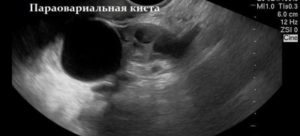

Параовариальная киста яичника и беременность никак друг другу не мешают до тех пор, пока новообразование не начнет увеличиваться. На начальной стадии ведется постоянное наблюдение. Если киста начала расти – хирургическое вмешательство обязательно.

- параовариальная. Такая киста опасна разрывом и перекрутом ножки, нагноением и развитием острого живота. Она может развиться у женщин любого возраста из-за неправильного развития придаточных канальцев. Опухоль имеет вид полости в придатке, выстланной эпителиальной тканью, которая заполнена муциозным веществом с экссудатом. Поскольку кисту снабжают кровью сосуды стенок матки и ее труб, она может спровоцировать их деформирование. Единственным положительным моментом является то, что данный вид новообразований не становится злокачественным;

Еще одно образование, которое часто встречается у женщин в период вынашивания плода — параовариальная капсула. Если был установлен точный диагноз, то с зачатием необходимо повременить.

При беременности с параовариальной кистой повышается риск нагноения, разрыва стенок, сдавления плода.

Растет параовариальная киста при беременности быстро, повышается риск разрыва стенок и перекручивания её ножки на поздних сроках и во время родов.